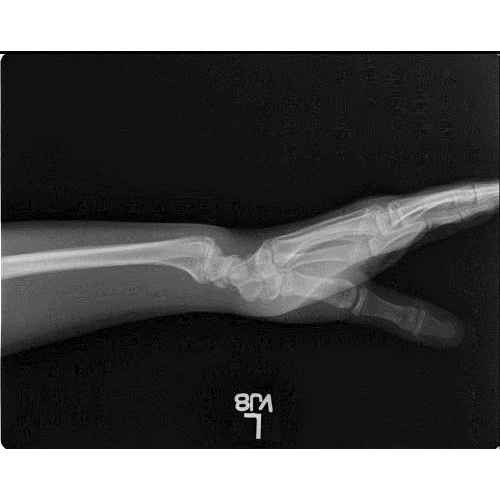

(A) Lateral and (B) AP radiographs in a gymnast with wrist pain. There Wrist Pain In Young Gymnasts Gymnast's wrist is a distal radius physeal injury most commonly due to overuse of the wrist primarily affecting young gymnasts. Diagnosis is made clinically with tenderness at the. Gymnast’s wrist is irritation and inflammation of the growth plate (epiphysis) at the end of the radius (forearm bone) where it connects to the hand to. Wrist pain among young, nonelite gymnasts. Wrist Pain In Young Gymnasts.